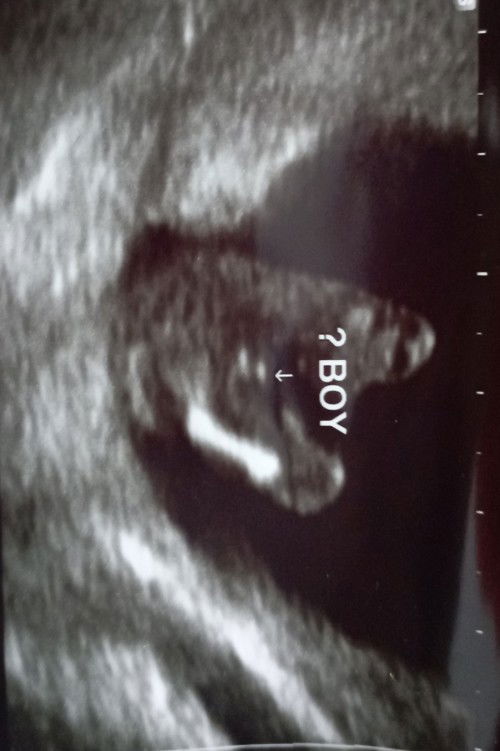

baby boy ka ni

hai mommies semua...saya baru 13 week 3 day... saja p scan lepastu doctor saja scan jantina dia cakap maybe baby boy...kalau macam ni memang boy ka#firstbaby

kalau mcm ni xjelas lagi ... mcm saya 14 weeks dia tunjuk btl2 mcm pistol .. ni dah masuk 26 weeks dah 3 kali scan pun boy .. sis try lagi dlm 2-3 minggu nnt dia akan tunjuk kalau boy

Blm boleh dipastikan lg sis. Bleh jd sign burger, boleh jadi scrotum dia. Heee smoga diprmudhkn yaa. 18 bleh scan lg skli confirmkn.